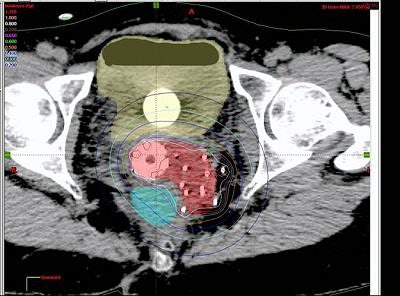

| Tumor volume on MRI (above) and CT (below). Images courtesy of Dr. Akila Viswanathan. |

Based on the DVH analysis -- done with CT volumes because that is the standard, Viswanathan added -- the median tumor volume was 80 cc. The median V150 was 60%, the median V90 was 82%, and the median V95 was 90%.

"For bladder and rectal DVHs, we saw that the median bladder total volume was 68 cc. We then calculated the 2-cc and 5-cc percent-of-treatment to the bladder volume and it was 80% and 70%, respectively," she said. "The median rectal volume was contoured for 55 cc and we saw that the 2-cc and 5-cc volumes were 90% and 80% of our prescription."

"We concluded that MR-guided interstitial brachytherapy is feasible. It does prevent the insertion into the bladder and rectum. It does allow conformal treatment planning and accurate delineation of the tumor, bladder, and rectum," she stated.